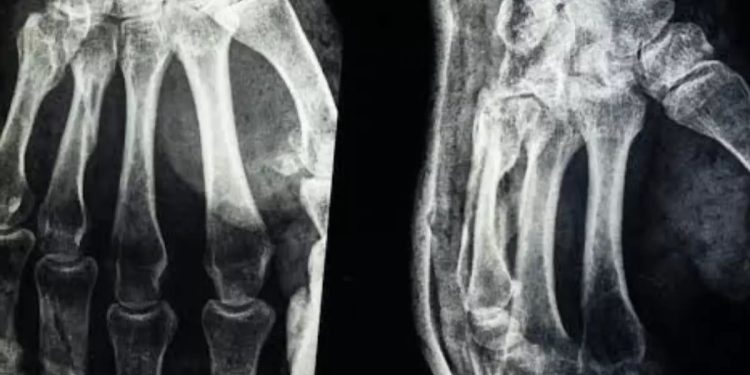

Las fracturas obligan al cuerpo a atravesar un proceso lento que exige semanas o meses de inmovilización, genera incomodidad en la vida diaria y responde al ciclo natural de regeneración ósea. El organismo produce callo óseo y remodela la zona dañada a lo largo de un periodo prolongado, lo que condiciona la movilidad del paciente y su calidad de vida.

La investigación superó ya varias fases clínicas. Más de 150 pacientes participaron en las pruebas y los resultados fueron alentadores. En un informe recogido por Global Times se destacó que los huesos tratados soportaron más de 180 kilos de fuerza. También se midieron una resistencia al corte de 0,5 MPa y una resistencia a la compresión cercana a 10 MPa. Valores así indican que el adhesivo puede igualar la estabilidad de sistemas convencionales sin necesidad de colocar placas de acero.

The Economics Times señaló que los ensayos clínicos descartaron efectos adversos de toxicidad o inflamación. El producto mostró seguridad en su aplicación y además mantuvo una resistencia considerable frente a fuerzas externas. Esa combinación de eficacia y tolerancia abre la puerta a un cambio en la forma de tratar fracturas complicadas. Procedimientos que hasta ahora requerían horas de cirugía con implantes metálicos pudieron resolverse en apenas minutos.